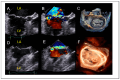

Mitral regurgitation (MR) is a common valvular heart disease associated with significant morbidity and mortality. For patients at high or prohibitive surgical risk, mitral transcatheter edge-to-edge repair (M-TEER) offers a less invasive alternative to surgery. This review outlines key aspects of patient selection and procedural planning for M-TEER, with a focus on clinical and echocardiographic criteria essential for success. Comprehensive imaging-especially 2D and 3D transesophageal echocardiography-is critical to assess leaflet anatomy, coaptation geometry, and mitral valve area. Selection criteria differ between primary and secondary MR and are guided by trials such as COAPT and MITRA-FR. Optimal outcomes rely on careful screening, anatomical suitability, and multidisciplinary evaluation. With growing experience and advancing technology, M-TEER has become a transformative option for treating severe MR in non-surgical candidates.